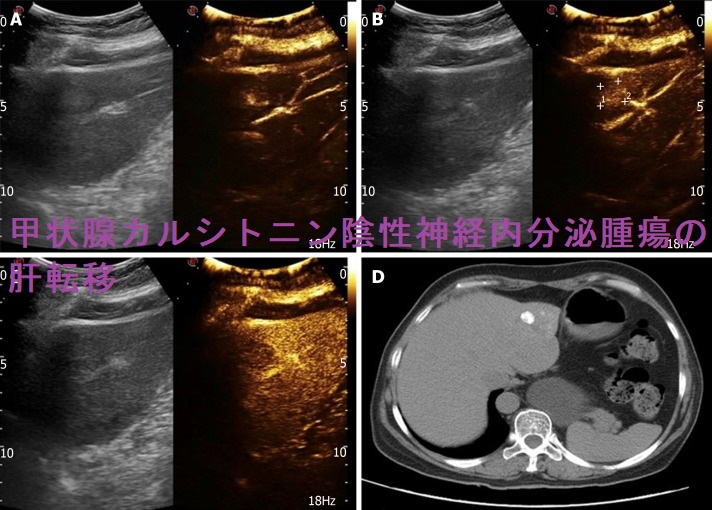

また、甲状腺カルシトニン陰性神経内分泌腫瘍の肝転移巣に経カテーテル動脈化学塞栓術(TACE)を施行したが、治癒効果不十分だった報告もあります。[World J Clin Cases. 2020 Jan 6;8(1):179-187.]

甲状腺カルシトニン陰性神経内分泌腫瘍 超音波(エコー)画;Dは転移リンパ節

甲状腺カルシトニン陰性神経内分泌腫瘍の肝転移巣